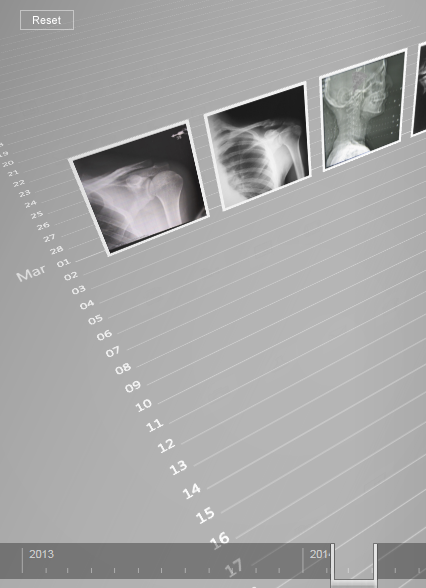

Scenario design, planning, and asset creation for future/vision videos at Microsoft. I also created demos and artifacts that could be experienced firsthand.

Digital Kitchen shot the videos, recruited cast, scouted locations, and added VFX.

︎ UX

︎ Storyboards

︎ Fake UI

︎ Engineering C#

Digital Kitchen shot the videos, recruited cast, scouted locations, and added VFX.

︎ UX

︎ Storyboards

︎ Fake UI

︎ Engineering C#